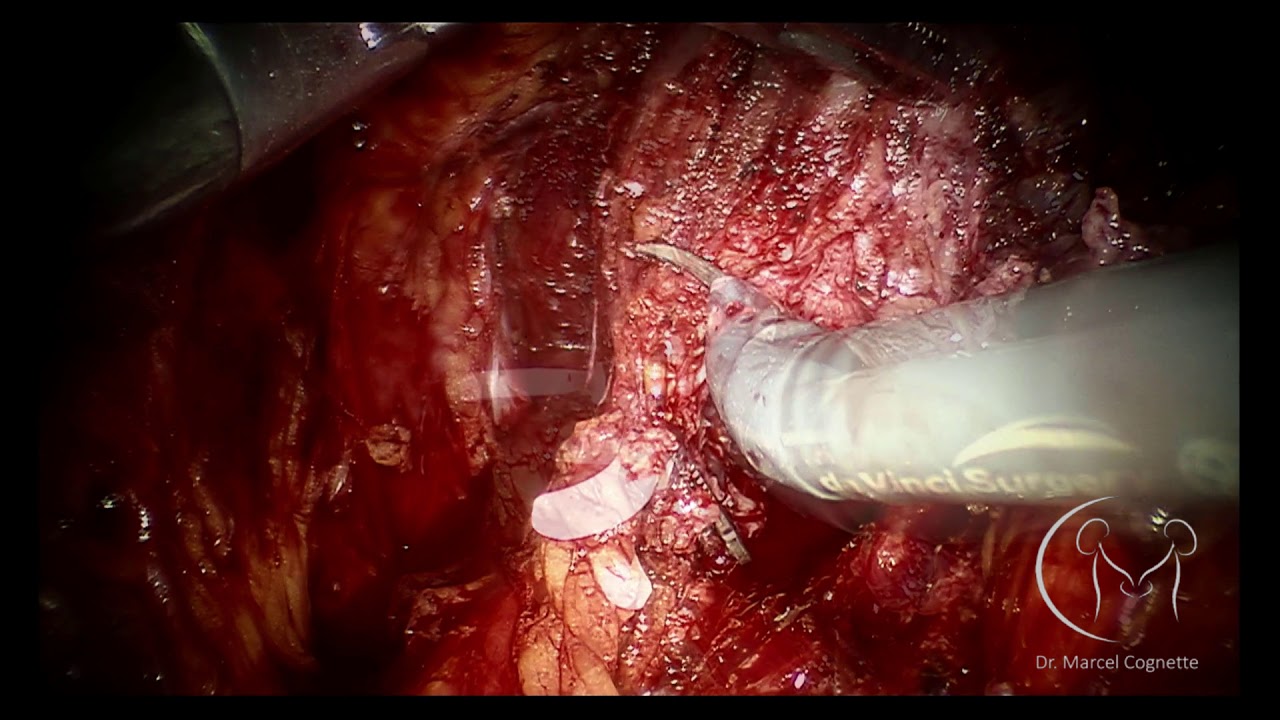

Minha especialidade é a uro-oncologia, área da medicina que se dedica ao diagnóstico e tratamento de tumores do sistema urinário masculino e feminino. Sou um dos poucos urologistas em Goiânia com vasta experiência em cirurgia robótica de próstata, rim e bexiga, uma técnica minimamente invasiva que oferece diversos benefícios aos pacientes, como:

Especialização – Fellow em Uro Oncologia e cirurgia minimamente invasiva com ênfase em Laparoscopia e Robótica pelo Hospital de Câncer de Barretos;

Especialização – Short Observership Florida Hospital Global Robotics Institute;

Certificado de Cirurgião Robótico de Console plataformas Si / Xi pela Intuitive ;

• cirurgia robótica